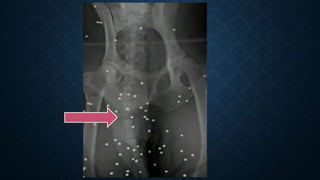

WHITE SPOTS

• Causes:

a) Pitted screen.

b) Dust, grit or any other material with radiopaque base present on film,

screens, grid or the animal.

c) Crescent marks due to folding of film before exposure.

d) Splash of water or fixer on film before processing.

e) Trapping of air bubbles on film's surface (air bells) during development.

f) Scratches on emulsion.